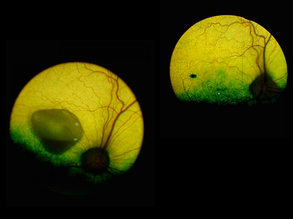

Blind Spot

Good Optics